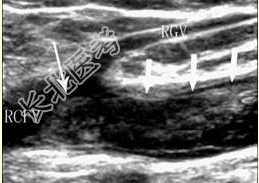

- [材料题] 患者女,50岁,因“右下肢水肿、胀痛3d”来诊。超声图像如下。

- 简答题1、患者的诊断及依据是什么?

- 简答题2、该患者在进行超声检查时应注意避免什么?